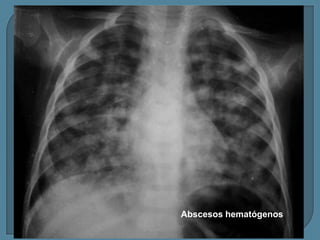

Abscesos hematógenos